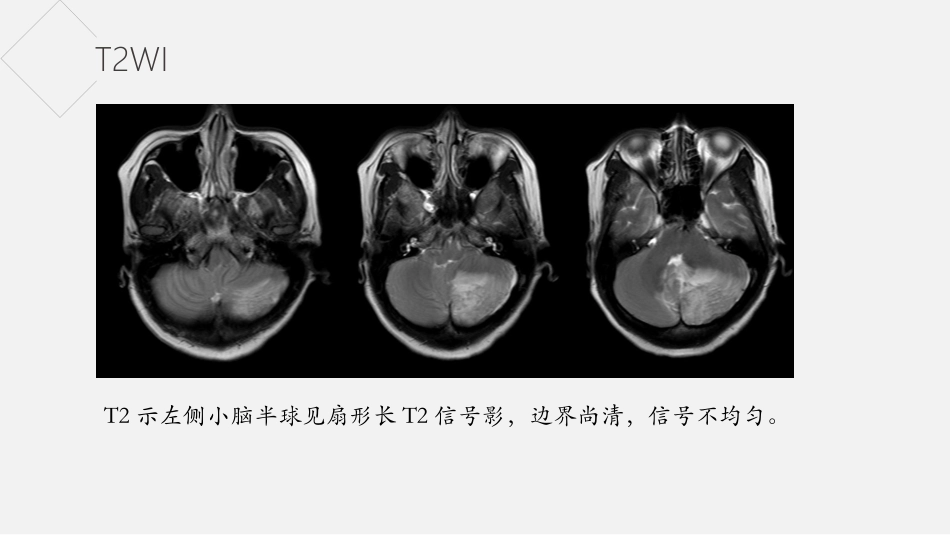

病史女,42岁,3天前无明显诱因出现头晕不适,精神食欲差,当地医院提示左侧小脑半球占位性病变。T2WIT2示左侧小脑半球见扇形长T2信号影,边界尚清,信号不均匀。T1WIT1示左侧小脑半球见扇形长T1信号影,边界尚清,信号不均匀。DWIADCDWI示左侧小脑半球病灶呈稍高信号,ADC示病灶部分呈低信号。增强增强示病灶未见明显强化。小脑发育不良神经节细胞瘤小脑发育不良神经节细胞瘤概述Padberg等人认为小脑发育不良神经节细胞瘤与多发性错构瘤综合征(MHAM)(也称为Cowden综合征(CS))共存的观点,认为PTEN基因突变是导致CS的主要原因。CS是一种常染色体显性遗传性癌症综合征,其特征在于通过与乳腺癌,甲状腺癌和泌尿生殖恶性肿瘤、全身错构瘤等高发生率相关联的神经皮肤综合征。2007年WHO分类中将本病归属神经元和混合性神经元的神经胶质肿瘤,并统一命名为小脑发育不良性神经节细胞瘤属良性肿瘤(WHOⅠ级)。小脑发育不良神经节细胞瘤临床症状本病进展较缓,早期症状轻微;部分患者无症状在体检时发现。其首发症状多以颅内高压症为主要表现,如头痛、恶心、呕吐、视物模糊等;其次为后组颅神经麻痹,小脑症状如共济失调、步态不稳等一般出现较晚。临床上常伴有多种先天发育畸形,如巨脑、脊髓积水、多指(趾)、多发血管瘤和颅骨异常。无明显性别及种族差异,年龄跨度较大,从出生至74岁均可发生,发病年龄高峰为30~50岁。小脑发育不良神经节细胞瘤病理组织学形态可见弥漫性增厚的小脑分子层和颗粒层内大量异常增生的神经节细胞,使小脑皮质增宽,但原有结构仍相对保留;分子层外可见平行排列的异常有髓纤维;浦肯野细胞减少或消失,亦可见扩张血管和钙化灶。免疫组织化学染色,异常神经节细胞胞核表达神经元核抗原(NeuN,图2)和突触素(Syn)、而不表达同源性磷酸酶张力蛋白(⁃PTEN),胶质纤维背景表达胶质纤维酸性蛋白(GFAP),神经纤维表达神经微丝蛋白(NF)。小脑发育不良神经节细胞瘤影像表现T2WI呈现高信号区域内有低信号的条纹状排列结构,T1WI呈等/低信号条纹,这种条纹排列结构称之为“虎纹征”。病灶边界清晰,周围无水肿。增强扫描病变无明显强化或轻微强化。通常伴梗阻性脑积水、小脑扁桃体疝、脊髓空洞。谢谢欣赏